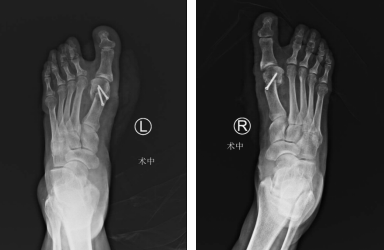

上周,足踝科大科主任石荣剑主任医师率领团队以精湛的技术完成两例微创手术,术后效果突出,赢得患者赞誉:采用第三代微创踇外翻矫正技术,为一位踇外翻畸形10多年的57岁患者成功进行了左右足矫正;利用踝关节镜,为一位扭伤右踝半年的49岁患者进行了镜下关节探查清理+距腓前韧带修复手术。

王大姐随即办理了入院手续,完善了相关术前检查,第二天,石荣剑副院长徐明亮主任魏笛医生手术团队为王大姐进行了右足踇外翻矫形术。手术采用第三代微创踇外翻矫正技术,进口超声磨锯进行骨赘削磨及微创截骨,切口仅数毫米,既稳又快地完成手术。王大姐第二天就下地行走了,第三天换药时几乎看不到伤口。五天出院,回家三周后,王大姐就又过来了,找到石院长提出给她的左脚踇外翻也做矫形。“矫形手术效果真的不错,我的右脚现在一点也不痛,还好看了不少,平时走个几里路、上楼下楼都轻轻松松,您这次把我的左脚也做了吧!”如今王大姐的左脚也完成了微创踇外翻矫形,已经出院回家。

第三代微创踇外翻手术,切口小于1厘米,进口超声磨锯进行骨赘削磨及截骨,组织创伤小,伤口及周围组织易于修复。术后恢复快,疤痕微小,康复时间短,早期下床行走,减少关节粘连,避免出现踇趾僵直。